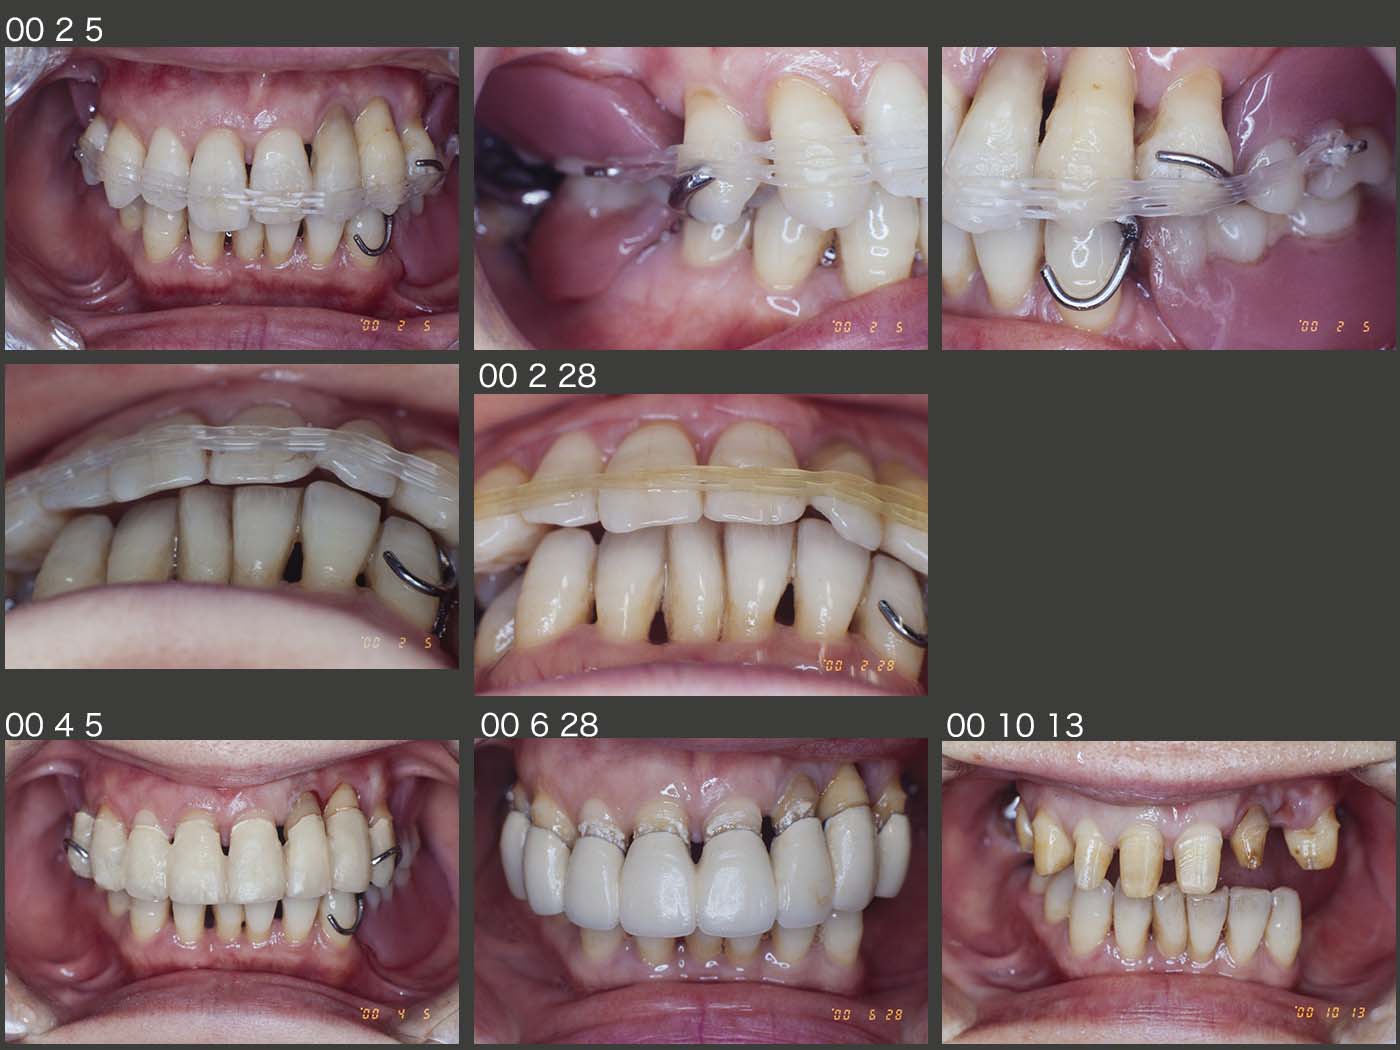

1999年3月初診,54歳女性.歯がグラグラする,義歯を装着したいが主訴.歯周基本治療を行いながら,まず保存不可能な上顎左右5を抜去し,上顎残存歯に暫間固定を施した.8月,上顎に暫間義歯を装着した.続いて,右下6の遠心根をヘミセクションし,近心根および左下4を残根状としたうえで,12月,下顎に暫間義歯を装着した.(2000年3月,左下4は予後不良にて抜去した.)

2000年2月,上顎前歯がフレアアウトしていたため,暫間義歯にゴムのかかるフックを付与し,患者さん自身にゴムの脱着をお願いして,上顎前歯が下顎前歯と咬合するまで継続して貰った.なお,期間は約3週間で済んだ.残存歯を有髄歯のまま保存したかったので,マージンの位置を高くして形成し,4月に連結固定した暫間被覆冠を装着した.その後,最終印象を行い,メタルボンド冠を試適した際,左上3が挻出してしまった.これは被覆冠を撤去する際に脱臼してしまった可能性が高い.6月,残念ながら左上3を抜去し,10月まで抜歯窩の治癒を待った.